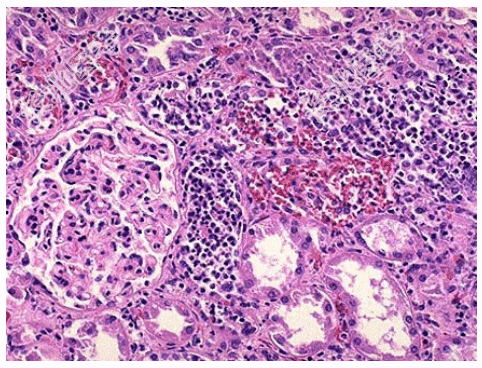

- [材料题] 死者,女性,28岁。因败血症死亡。发病初期曾有持续发热、腰痛、尿频、尿急、脓尿等症状。尸检见双肾肿大,包膜紧张,肾盂肾盏黏膜充血、水肿、表面有脓性分泌物,并可见小脓肿(如图),镜检如图所示。